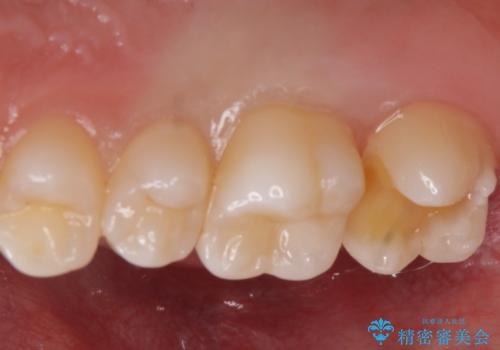

歯と歯の間の虫歯 e-maxインレーで修復

- 歯と歯の間に虫歯が見られたために、拡大鏡下でう蝕を取り除き、e-maxインレーで治療しました。

- e-maxインレー 7.7万円 費用は治療当時の料金となります

セラミックの素材は樹脂の素材に比べて虫歯の再発のリスクが低いです。